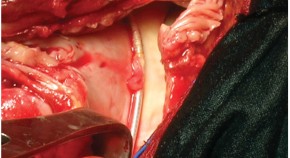

• In this month's Case Study, Versaci and colleagues present a case of congenital coronary artery fistula originating from the left anterior coronary artery and draining into right ventricle, in conjunction with an aneurysm of the left anterior descending artery. The high risk of rupture lead the authors to close the fistula surgically using normothermic cardiopulmonary bypass.